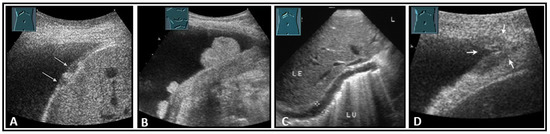

The diaphragm presents as a three-layered structure with external bounding pleural and peritoneal membranes and a muscular layer [60]. The diaphragm thickness varies depending on breathing, among other factors. Transhepatic acoustic radiation and visualization of the diaphragmatic rib angles are of particular importance. In patients with chronic obstructive pulmonary disease, diaphragmatic hypertrophy and/or diaphragmatic furrows can be demonstrated as pseudotumors (Figure 33). In tumor staging, visualization of the diaphragm should be performed to exclude or prove diaphragmatic metastases and areal and nodular lesions can be differentiated (Figure 34).

Figure 34.

Illustration of nodular (A: hypoechoic flat (arrow); B: hyperechoic polypoid) and flat diaphragmatic metastases (C, between markers) and a metastasis (arrow) in the diaphragmatic rib angle (D). LE: liver; LU: lung.